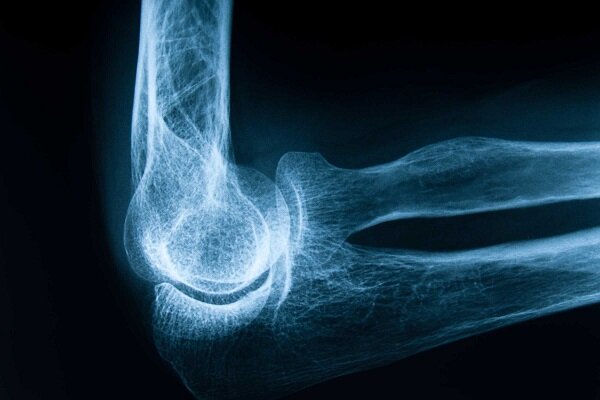

فرح اسماعیلی در گفت وگو با خبرنگار ایمنا، درباره اهمیت پیشگیری از پوکی استخوان و راه های ساده و موثر برای حفظ سلامت استخوان ها، اظهار کرد: پوکی استخوان بی سر و صدا پیشرفت می کند و تا زمانی که شکستگی رخ ندهد، ممکن است فرد متوجه آن نشود، اما وقتی با یک ضربه ساده یا حتی عطسه استخوان می شکند، افراد متوجه می شوند که تراکم استخوان آن ها کاهش یافته است.

وی با اشاره به بار مالی و روانی پوکی استخوان و تاکید بر ضرورت پیشگیری از این بیماری، تشخیص و درمان به موقع آن، افزود: شکستگی های ناشی از پوکی استخوان به ویژه در ناحیه لگن یا ستون فقرات می تواند منجر به جراحی های سنگین، بستری طولانی مدت، ناتوانی حرکتی و حتی افسردگی در سالمندان شود، بلکه این آسیب ها تنها بر سلامتی و آسیب های فردی نیست، بلکه نباید تنها هزینه های سنگینی بر سلامتی فرد وارد کند. خانواده ها انجام می دهد